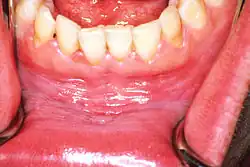

![]() | |

| Leukoplakia on the inside of the cheek | |

Oral leukoplakia is a potentially malignant disorder affecting the oral mucosa. It is defined as "essentially an oral mucosal white/gray lesion that cannot be considered as any other definable lesion." Oral leukoplakia is a gray patch or plaque that develops in the oral cavity and is strongly associated with smoking.[8] Leukoplakia is a firmly attached white patch on a mucous membrane which is associated with increased risk of cancer.[4][5] The edges of the lesion are typically abrupt and the lesion changes with time.[4][6] Advanced forms may develop red patches.[6] There are generally no other symptoms.[9] It usually occurs within the mouth, although sometimes mucosa in other parts of the gastrointestinal tract, urinary tract, or genitals may be affected.[10][11][12]

Homogeneous leukoplakia (also termed "thick leukoplakia")[2] is usually well defined white patch of uniform, flat appearance and texture, although there may be superficial irregularities.[2][9] Homogeneous leukoplakia is usually slightly elevated compared to surrounding mucosa, and often has a fissured, wrinkled or corrugated surface texture,[2] with the texture generally consistent throughout the whole lesion. This term has no implications on the size of the lesion, which may be localized or extensive.[2] When homogeneous leukoplakia is palpated, it may feel leathery, dry, or like cracked mud.[2]